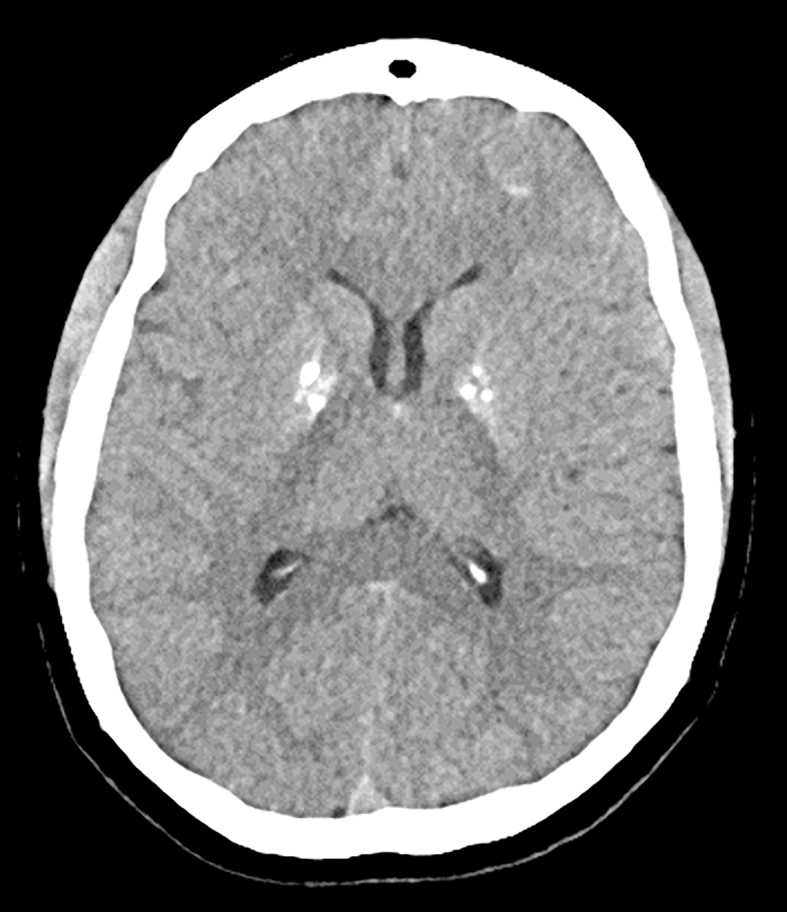

Summary: HDR syndrome is a rare, heterogeneous genetic disorder characterised by a triad of hypoparathyroidism, sensorineural deafness, and renal disease. The defect in most patients is caused by deletions in chromosome 10p14 or mutations in the GATA3 gene. HDR syndrome is also associated with several atypical features, including eye, skin, neurological, cardiac, gastrointestinal, and urogenital involvement. We report the case of a 27-year-old Caucasian woman with HDR syndrome (GATA3 NM_001002295.1: c.977C>A p. (Thr326Asn)), who presents with multiple atypical associated features. She has also had recurrent benign ovarian cystic teratomas, although it is unclear whether these are related to HDR syndrome, as this has never been reported.

Learning points: HDR syndrome is a rare autosomal genetic disorder characterised by a triad of hypoparathyroidism, sensorineural deafness, and renal disease. It may be associated with atypical features involving various organs, which will require investigation and management. There is a paucity of evidence and guidance on managing hypocalcaemia in HDR syndrome. Given that HDR syndrome causes agenesis rather than a receptor issue, calcium levels should be targeted between 2.0 and 2.2 mmol/L, similar to the management of hypoparathyroidism caused by surgery or autoimmune disease.